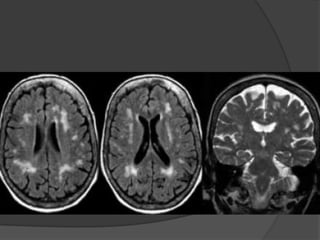

Fluid Attenuated Inversion Recovery

(FLAIR)



Special type of MRI scan

T1 image is inverted & added to

the T2 image

Contrast between grey & white

matter is doubled & the normal

CSF signal is suppressed.

Special indications

1.

To detect Sclerosis of

hippocampus in Temporal lobe

epilepsy.

2.

To Localize the areas of

abnormal metabolism in

degenerative neurological

diseases.

Diffusion-Weighted Imaging (DWI)

Sensitive to speed of

water diffusion

Visualizes area of

ischemic stroke in 1st

few hours- earliest to

detect ischemia.